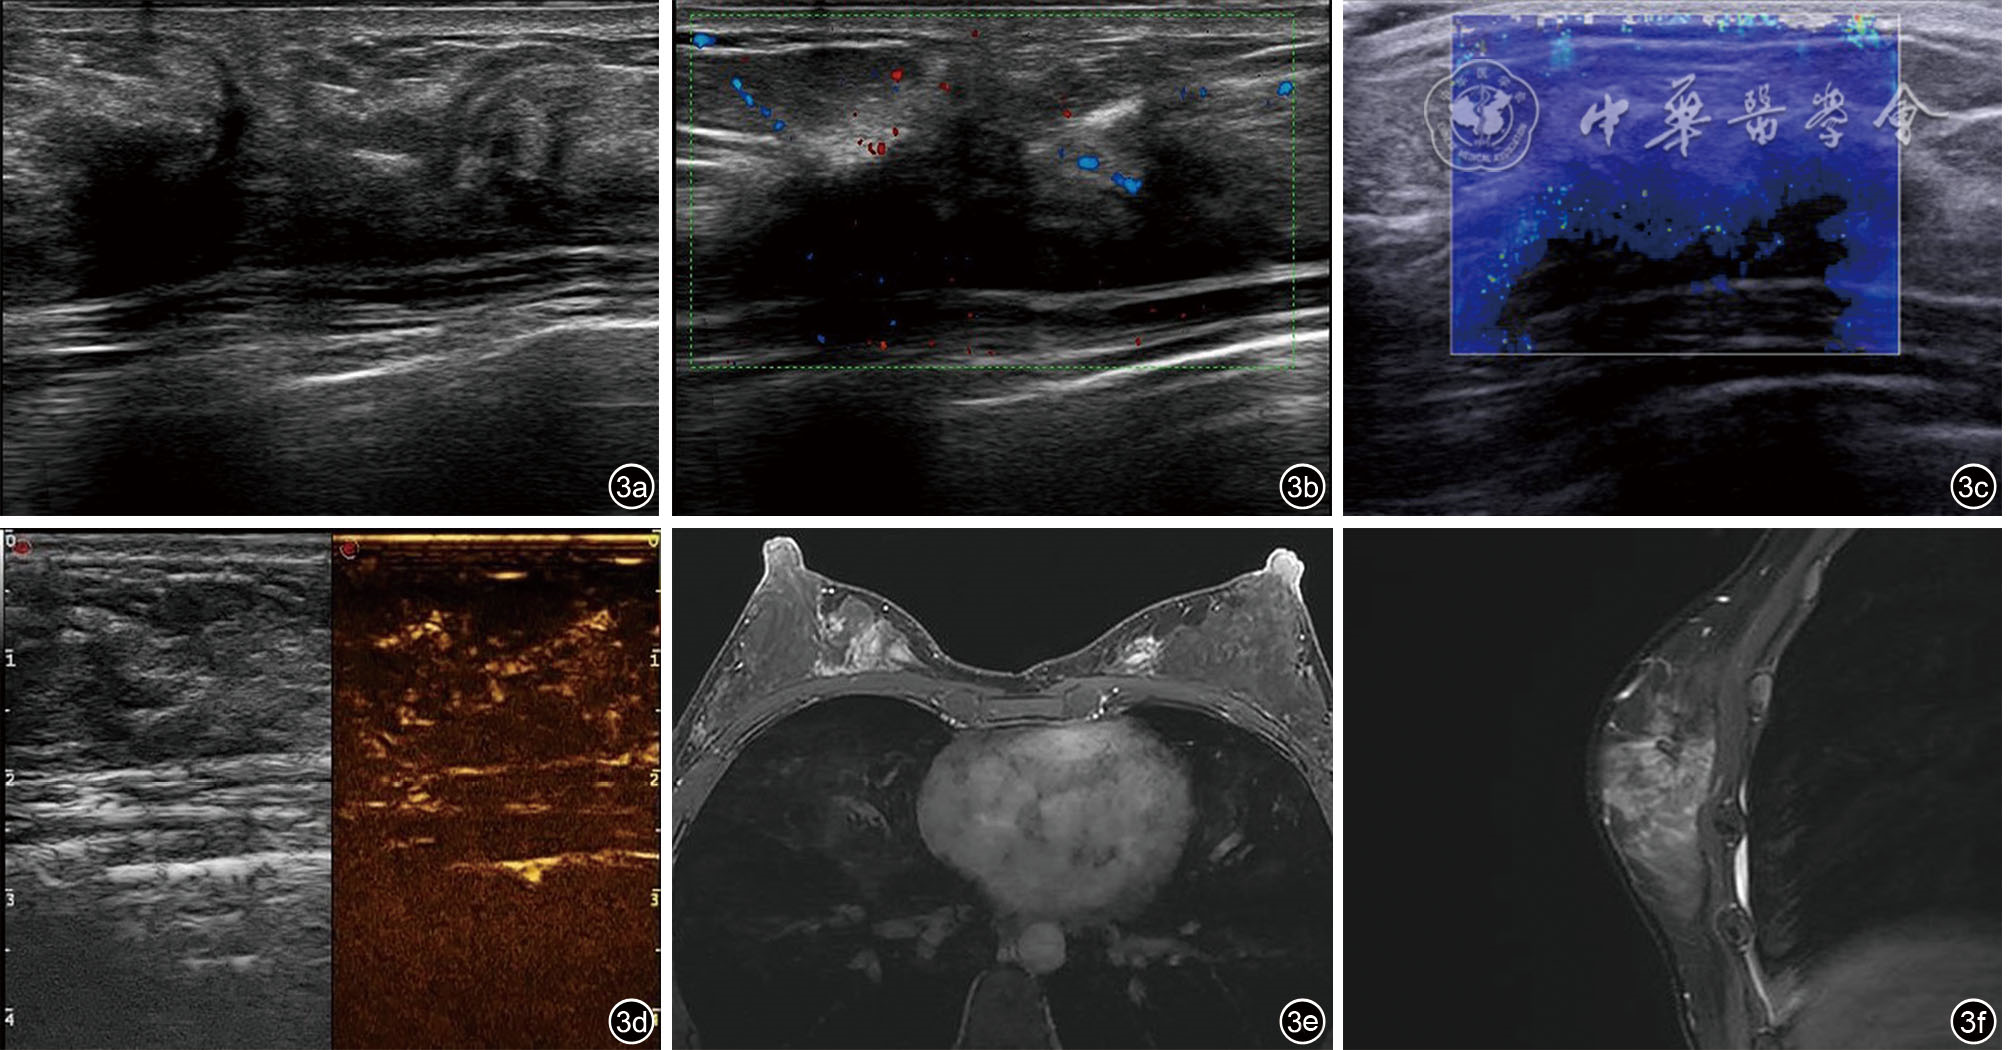

Liu H, Zeng H, Zhang H, et al. Breast fibromatosis: Imaging and clinical findings [J]. Breast J, 2020, 26(11): 2217-2222.

董叶, 彭晓静, 邓晶, 等. 高频超声诊断侵袭性纤维瘤病的应用价值 [J]. 临床超声医学杂志, 2021, 23(1): 69-72.

宗晴晴, 邓晶, 许迪. 乳腺纤维瘤病超声表现与病理结果对照研究及误诊分析 [J]. 肿瘤影像学, 2019, 28(6): 384-389.